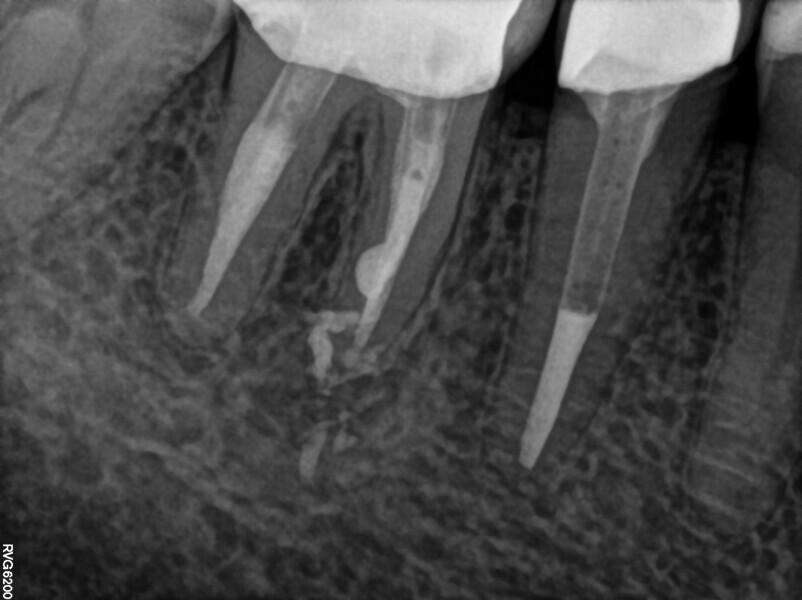

The patient was referred to Dr Witkowski’s dental office for endodontic treatment of teeth #31 and 41 (Fig. 2). After examination, endodontic treatment was performed (Fig. 3). In tooth #41, the access cavity was done by the referring dentist (Fig. 4a). In tooth #31, the access cavity was designed and performed (Fig. 4b). After this step, preparation of the canal space was done, in tooth #41 up to 25/0.04 and in tooth #31 up to 20/0.04 with VDW.ROTATE (VDW; Fig. 5). The next step was the irrigation protocol, which was performed with an Er,Cr:YSGG laser (BIOLASE) at 1.5 W and 100 Hz in both teeth. The canals were prepared for obturation. In tooth #41, obturation was done with a single point and CSBS, and in tooth #31, the piston technique was performed (Fig. 6). A control radiograph was taken immediately after the treatment (Fig. 7). Healing of the lesion was visible on the follow-up radiograph performed six months after the treatment (Fig. 8).

Fig. 7.